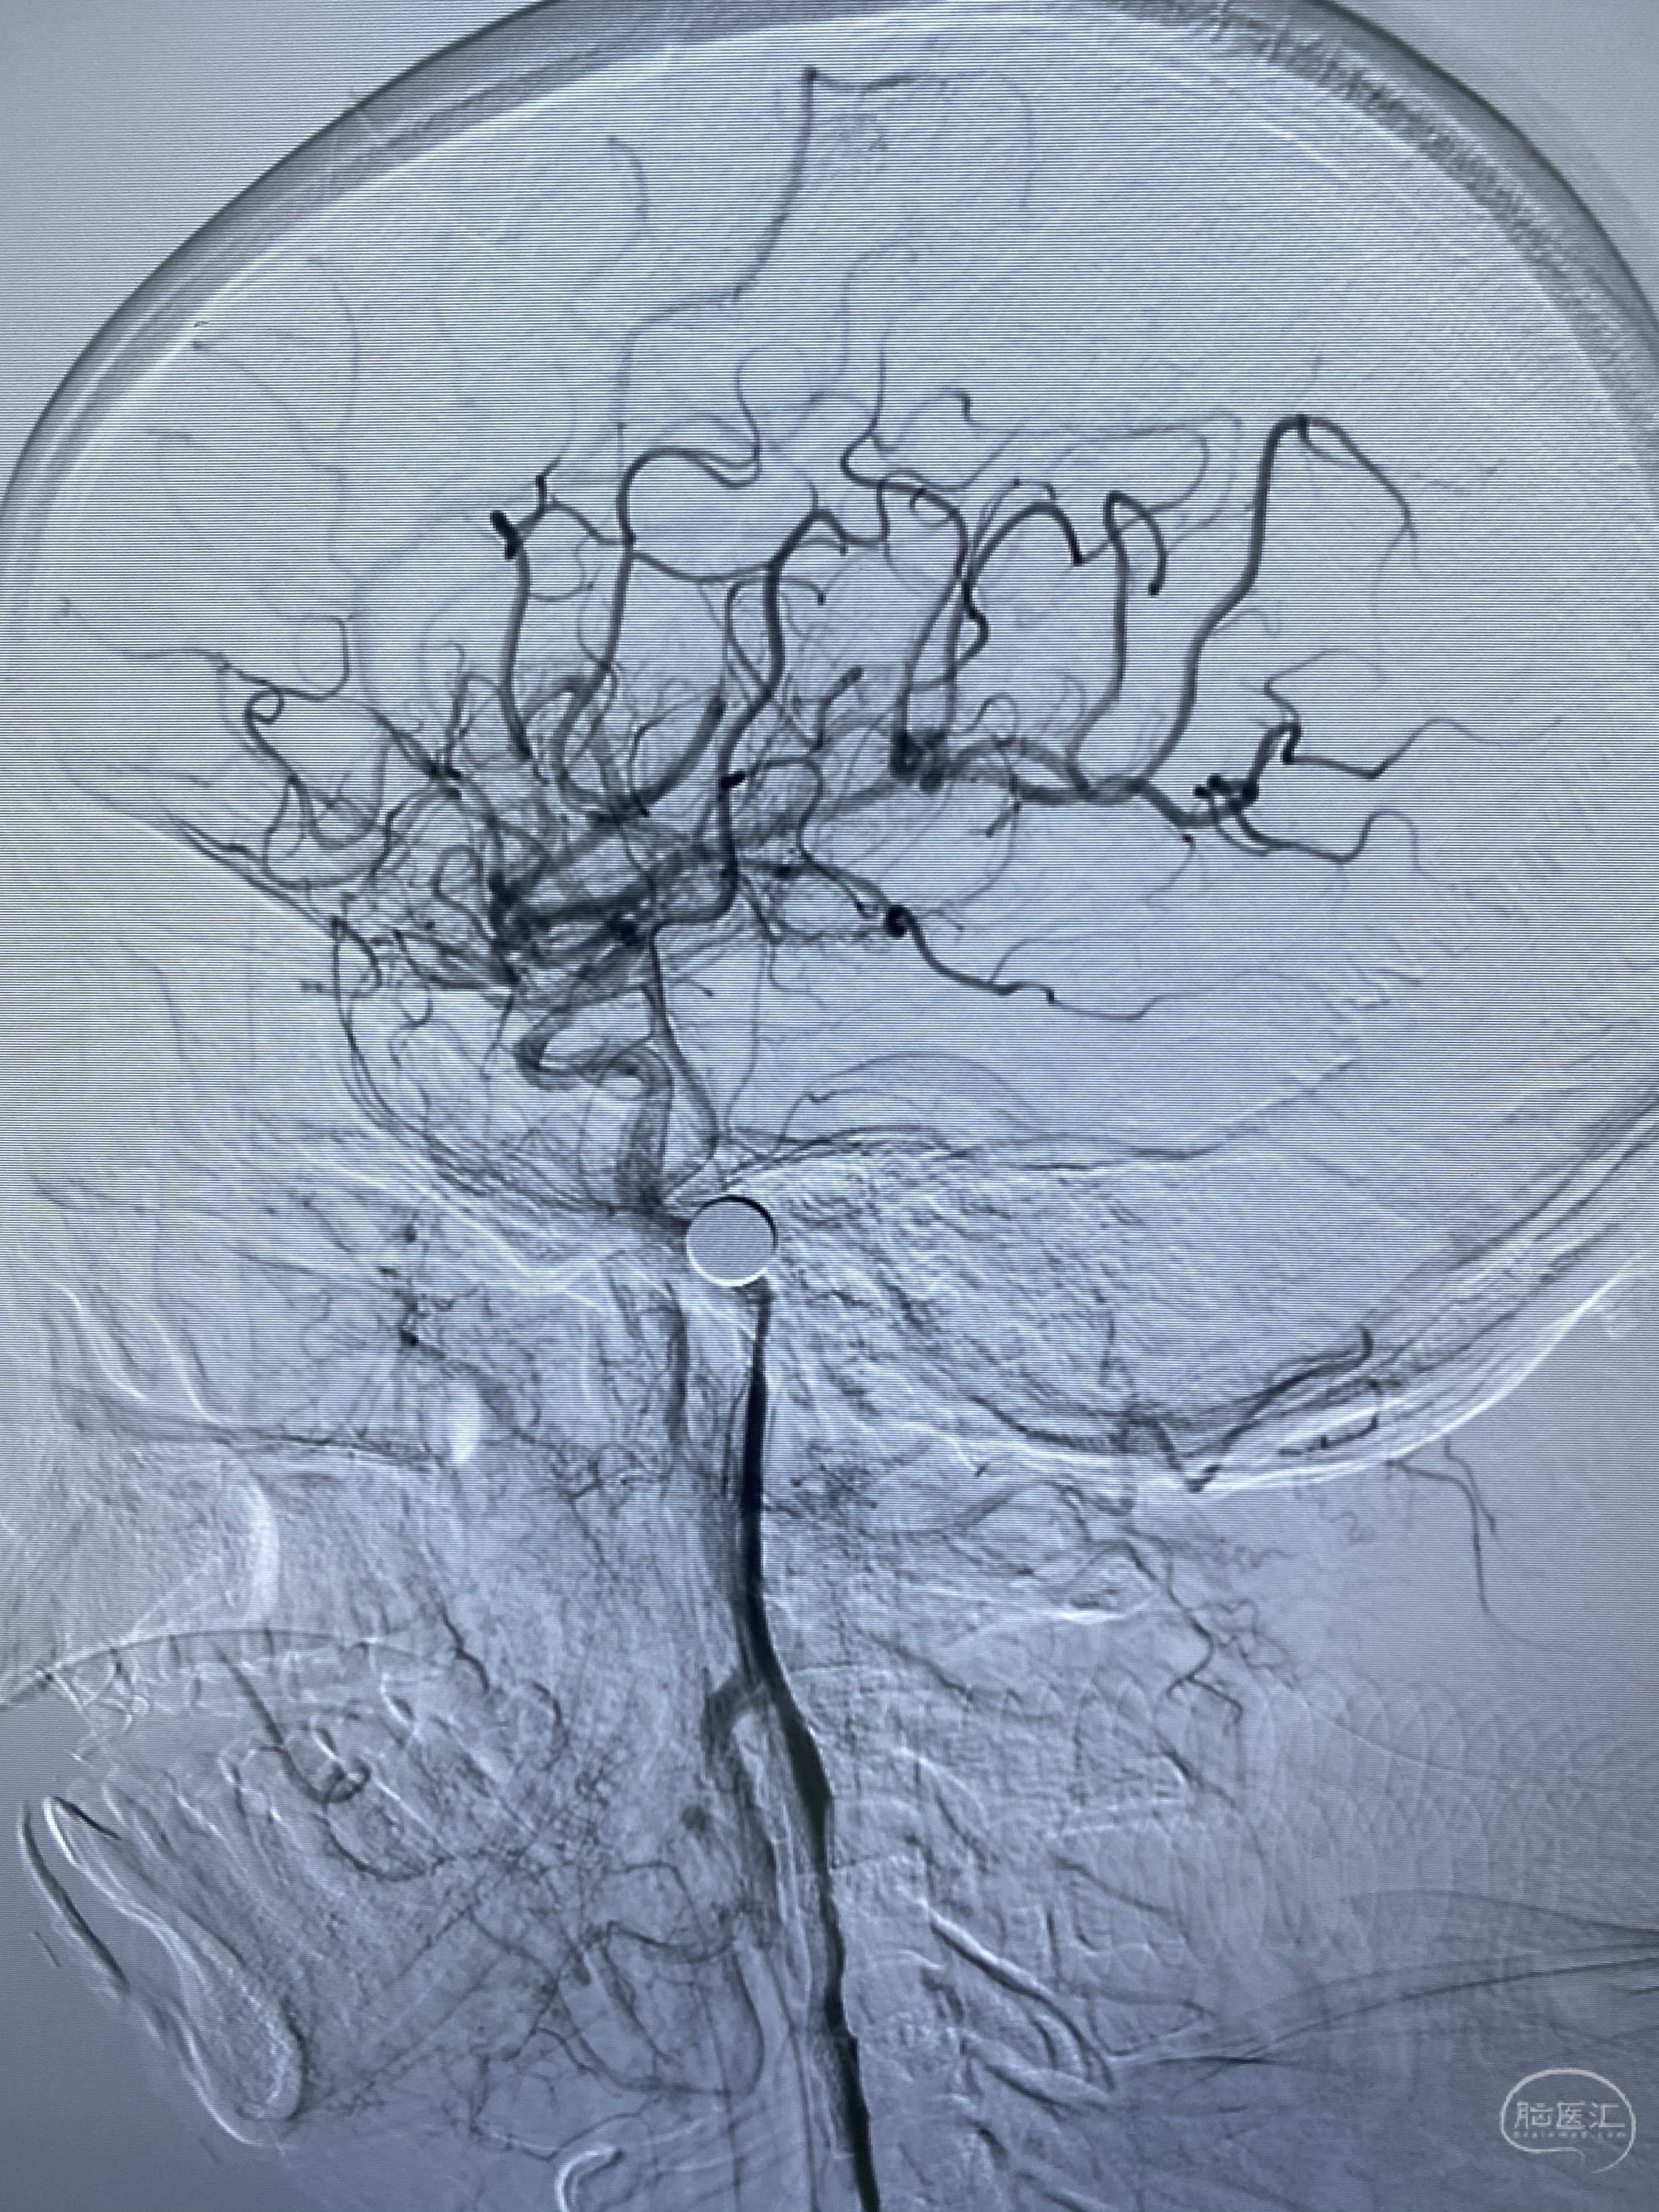

今日手术,TJG,M62Y,一期左侧颈动脉狭窄支架植入,二期椎动脉V4段多发夹层动脉瘤伴狭窄,常规支架辅助栓塞方法复杂又危险,血流导向装置植入快捷又安全。南阳市中心医院神经内科脑血管病介入团队pipeline flexFD植入两人导师资格。

椎动脉颅内段多发夹层动脉瘤伴载瘤动脉狭窄pipeline flex植入

今日手术,TJG,M62Y,一期左侧颈动脉狭窄支架植入,二期椎动脉V4段多发夹层动脉瘤伴狭窄,常规支架辅助栓塞方法复杂又危险,血流导向装置植入快捷又安全。南阳市中心医院神经内科脑血管病介入团队pipeline flexFD植入两人导师资格。